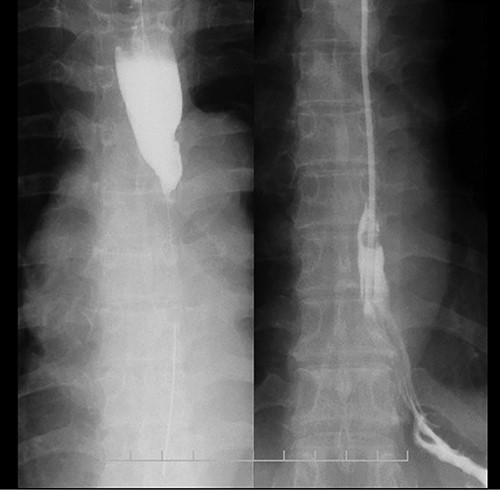

Coronal plane of the CT findings; CT demonstrates dilatation of the upper thoracic esophagus.

Preoperative computed tomography (CT) and barium meal studies were performed. The CT findings showed circumferential wall thickening with infiltrative change at the middle of the intrathoracic esophagus, with luminal dilation of the oral side of the stenotic esophagus (Figs 2, 3). The barium meal study showed no abnormal findings in the stomach (Fig. 4). Thoracoscopic esophagectomy was performed with the patient in the semi-prone position, followed by esophageal reconstruction using a gastric tube with the patient in the supine position. The operation was started with bilateral lung ventilation using a single-lumen endotracheal tube. A four-port thoracoscopic technique was used as follows: an observation port with a 10-mm scope was placed at the ninth intercostal space at the line of the inferior scapular angle, and two 5-mm ports and one 12-mm port for the intrathoracic procedures were placed at the third, fifth and seventh intercostal spaces, respectively, at the posterior axillary line (Fig. 5). Pneumothorax was created using 10 mmHg of CO2 to deflate the lung to achieve a better operative field. The pleura and connective tissue around the thoracic esophagus showed severe inflammatory and fibrotic changes. In particular, the middle thoracic esophagus was strongly adherent to the arch of the azygos vein and the tracheal bifurcation.